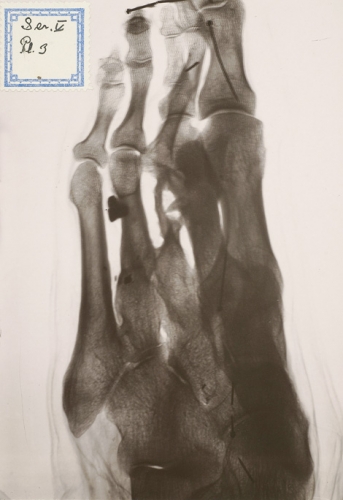

I sitt utlåtande beskriver Gösta Forsell bland annat en snedfraktur ungefär mitt på kungens vänstra lårben. Brottytan mäter 8 cm och är utan vinkelfelställning fastläkt med en tät kallusbildning med ett nybildat system av benbalkar. Förkortningen uppskattas till 3 cm. Karl XII:s kroppsmått mättes med millimeternoggrannhet och hans kroppslängd beräknas till 179 cm. Det högra benet från höftbenskammen till fotsulan var 1 100 mm och det vänstra 1 063 mm. Vidare konstaterar Forsell att »det finns en läkt skada vid basen av femte metatarsalbenet, läkta frakturer genom diafyserna på fjärde och andra metatarsalia samt defektläkt fraktur genom tredje metatarsen där den distala hälften av benet saknas. Man ser även en hel del kvarvarande metallfragment. Det finns vidare rikligt med benpålagringar på mellanfotsbenen, vilka tolkas som spår av kronisk infektion, både i benvävnaden som osteit och i angränsande mjukdelar.« (Den borttagna distala hälften av det tredje metatarsalbenet återfanns för övrigt i en sidenpåse i graven.)